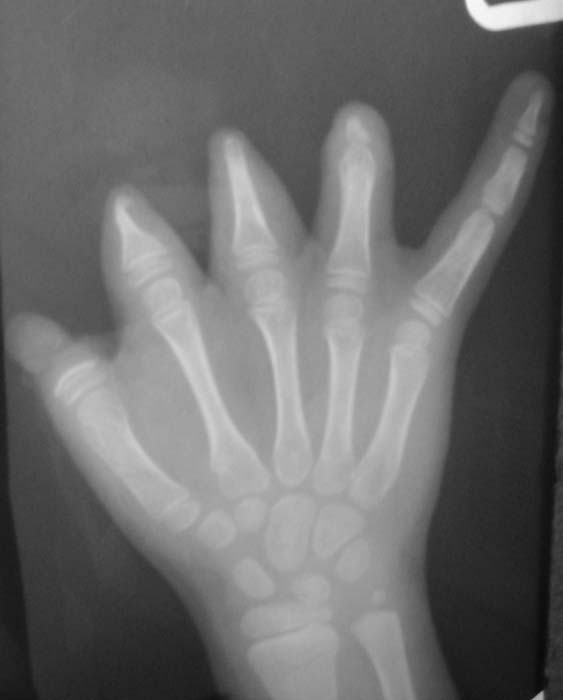

Уважаемые коллеги!Девочка, 6 лет. Врожденная аномалия развития кистей и стоп.Вопрос: лечение?В приложении - рентгенограммы и клинические фотографииЗаранее благодарен!С уважением,А.В.Владзимирский

Без рентгенограмм костей левой стопы, голени и голеностопного сустава определение тактики лечения левой нижней конечности невозможно. А с кистями рекомендую направить в специализированное отделение института им.Турнера (для удлинения фаланг пальцев с использованием микрохирургической техники)e-mail института им.Турнера: turner@admiral.ru

Безусловно девочке необходимо создать 1-й палец правой кисти - создать противопоставление остальным пальцем и таким образом получить функцию захвата. Варианты операций:

1. Пересадка 2-го пальца стопы (предварительно сделав доплерографию стопы и кисти)

2. Транспозиция культи 3 или 4-го пальца в положение 1-го.

3. Несвободная пересадка комплекса тканей на a. radialis в который входит участок лучевой кости (реверсионный лучевой лоскут с костным фрагментом для восстановления 1-го пальца.

4. Возможна свободная костная пластика (например, фрагмент в/3 большеберцовой кости кости с одновременной кожной пластикой по Блохину-Конверсу.

Обратите внимание на культю 2-го пальца - может необходимо резецировать острый костный конус с пластикой кожи над ней?